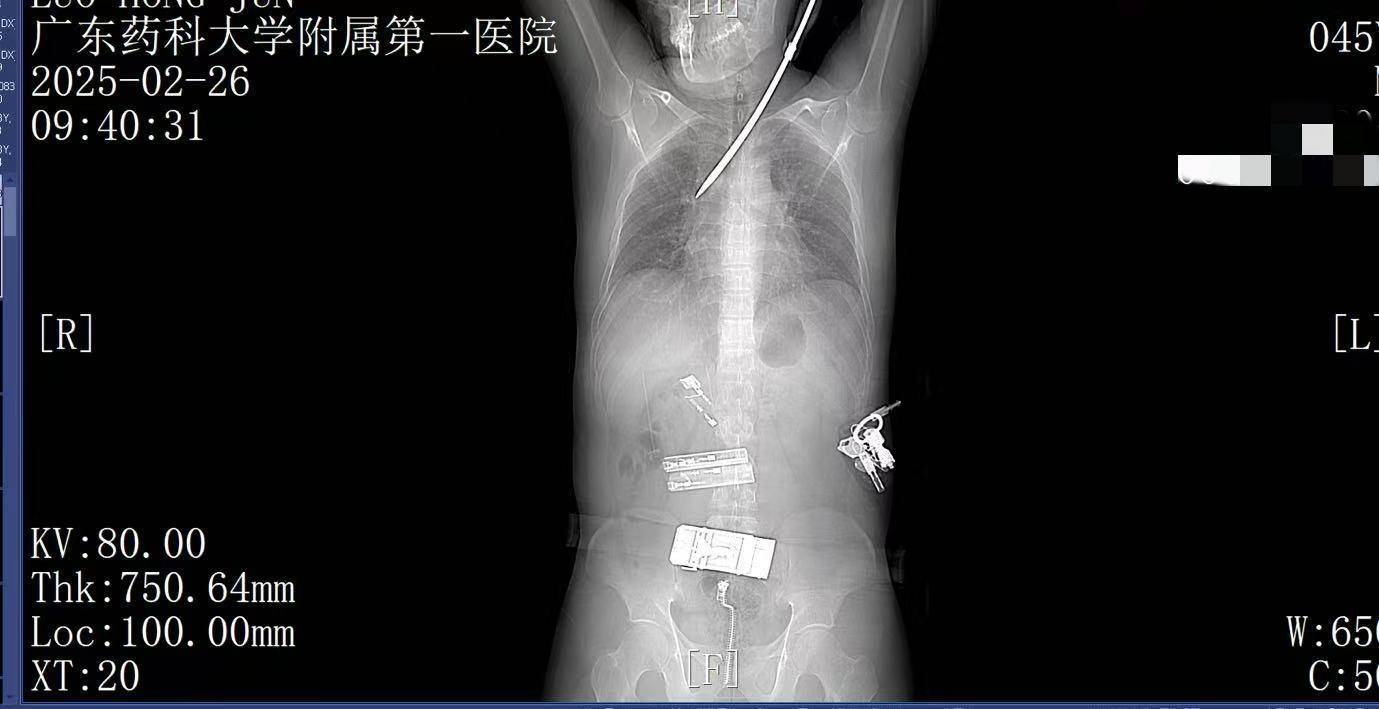

9:41,快速完成头+胸+腹部CT检查,经多学科会诊,明确螺丝刀异物刺入肺部上币保证金。CT显示螺丝刀紧贴肋间血管、上肺后段动脉,尖端距右肺门仅2厘米,一旦贸然拔出螺丝刀,极有可能引发大出血,导致失血性休克甚至死亡,必须紧急手术。

9:39,救护车到达医院大门,院内急救团队已经做好准备上币保证金。在紧密监护的情况下,全程采用绿色通道。到达医院时,罗师傅已经面色苍白,呼吸急促。螺丝刀已深深刺入罗师傅右肺,随时可能因大出血而危及生命。